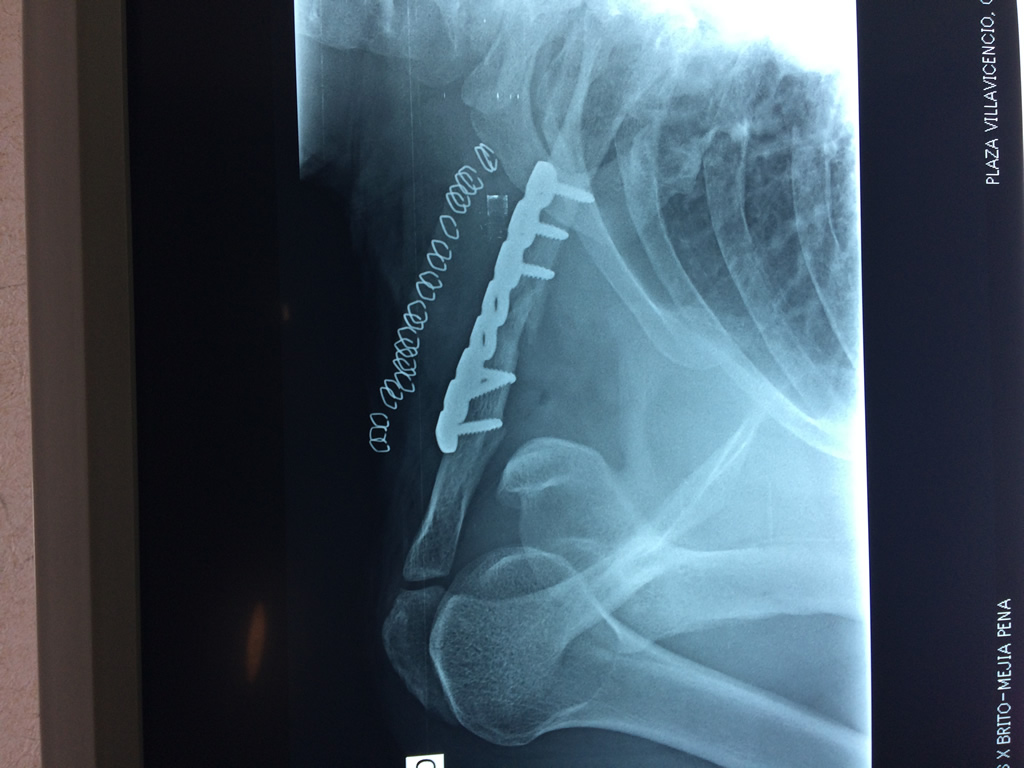

Cirugías de Hombros - Clavícula